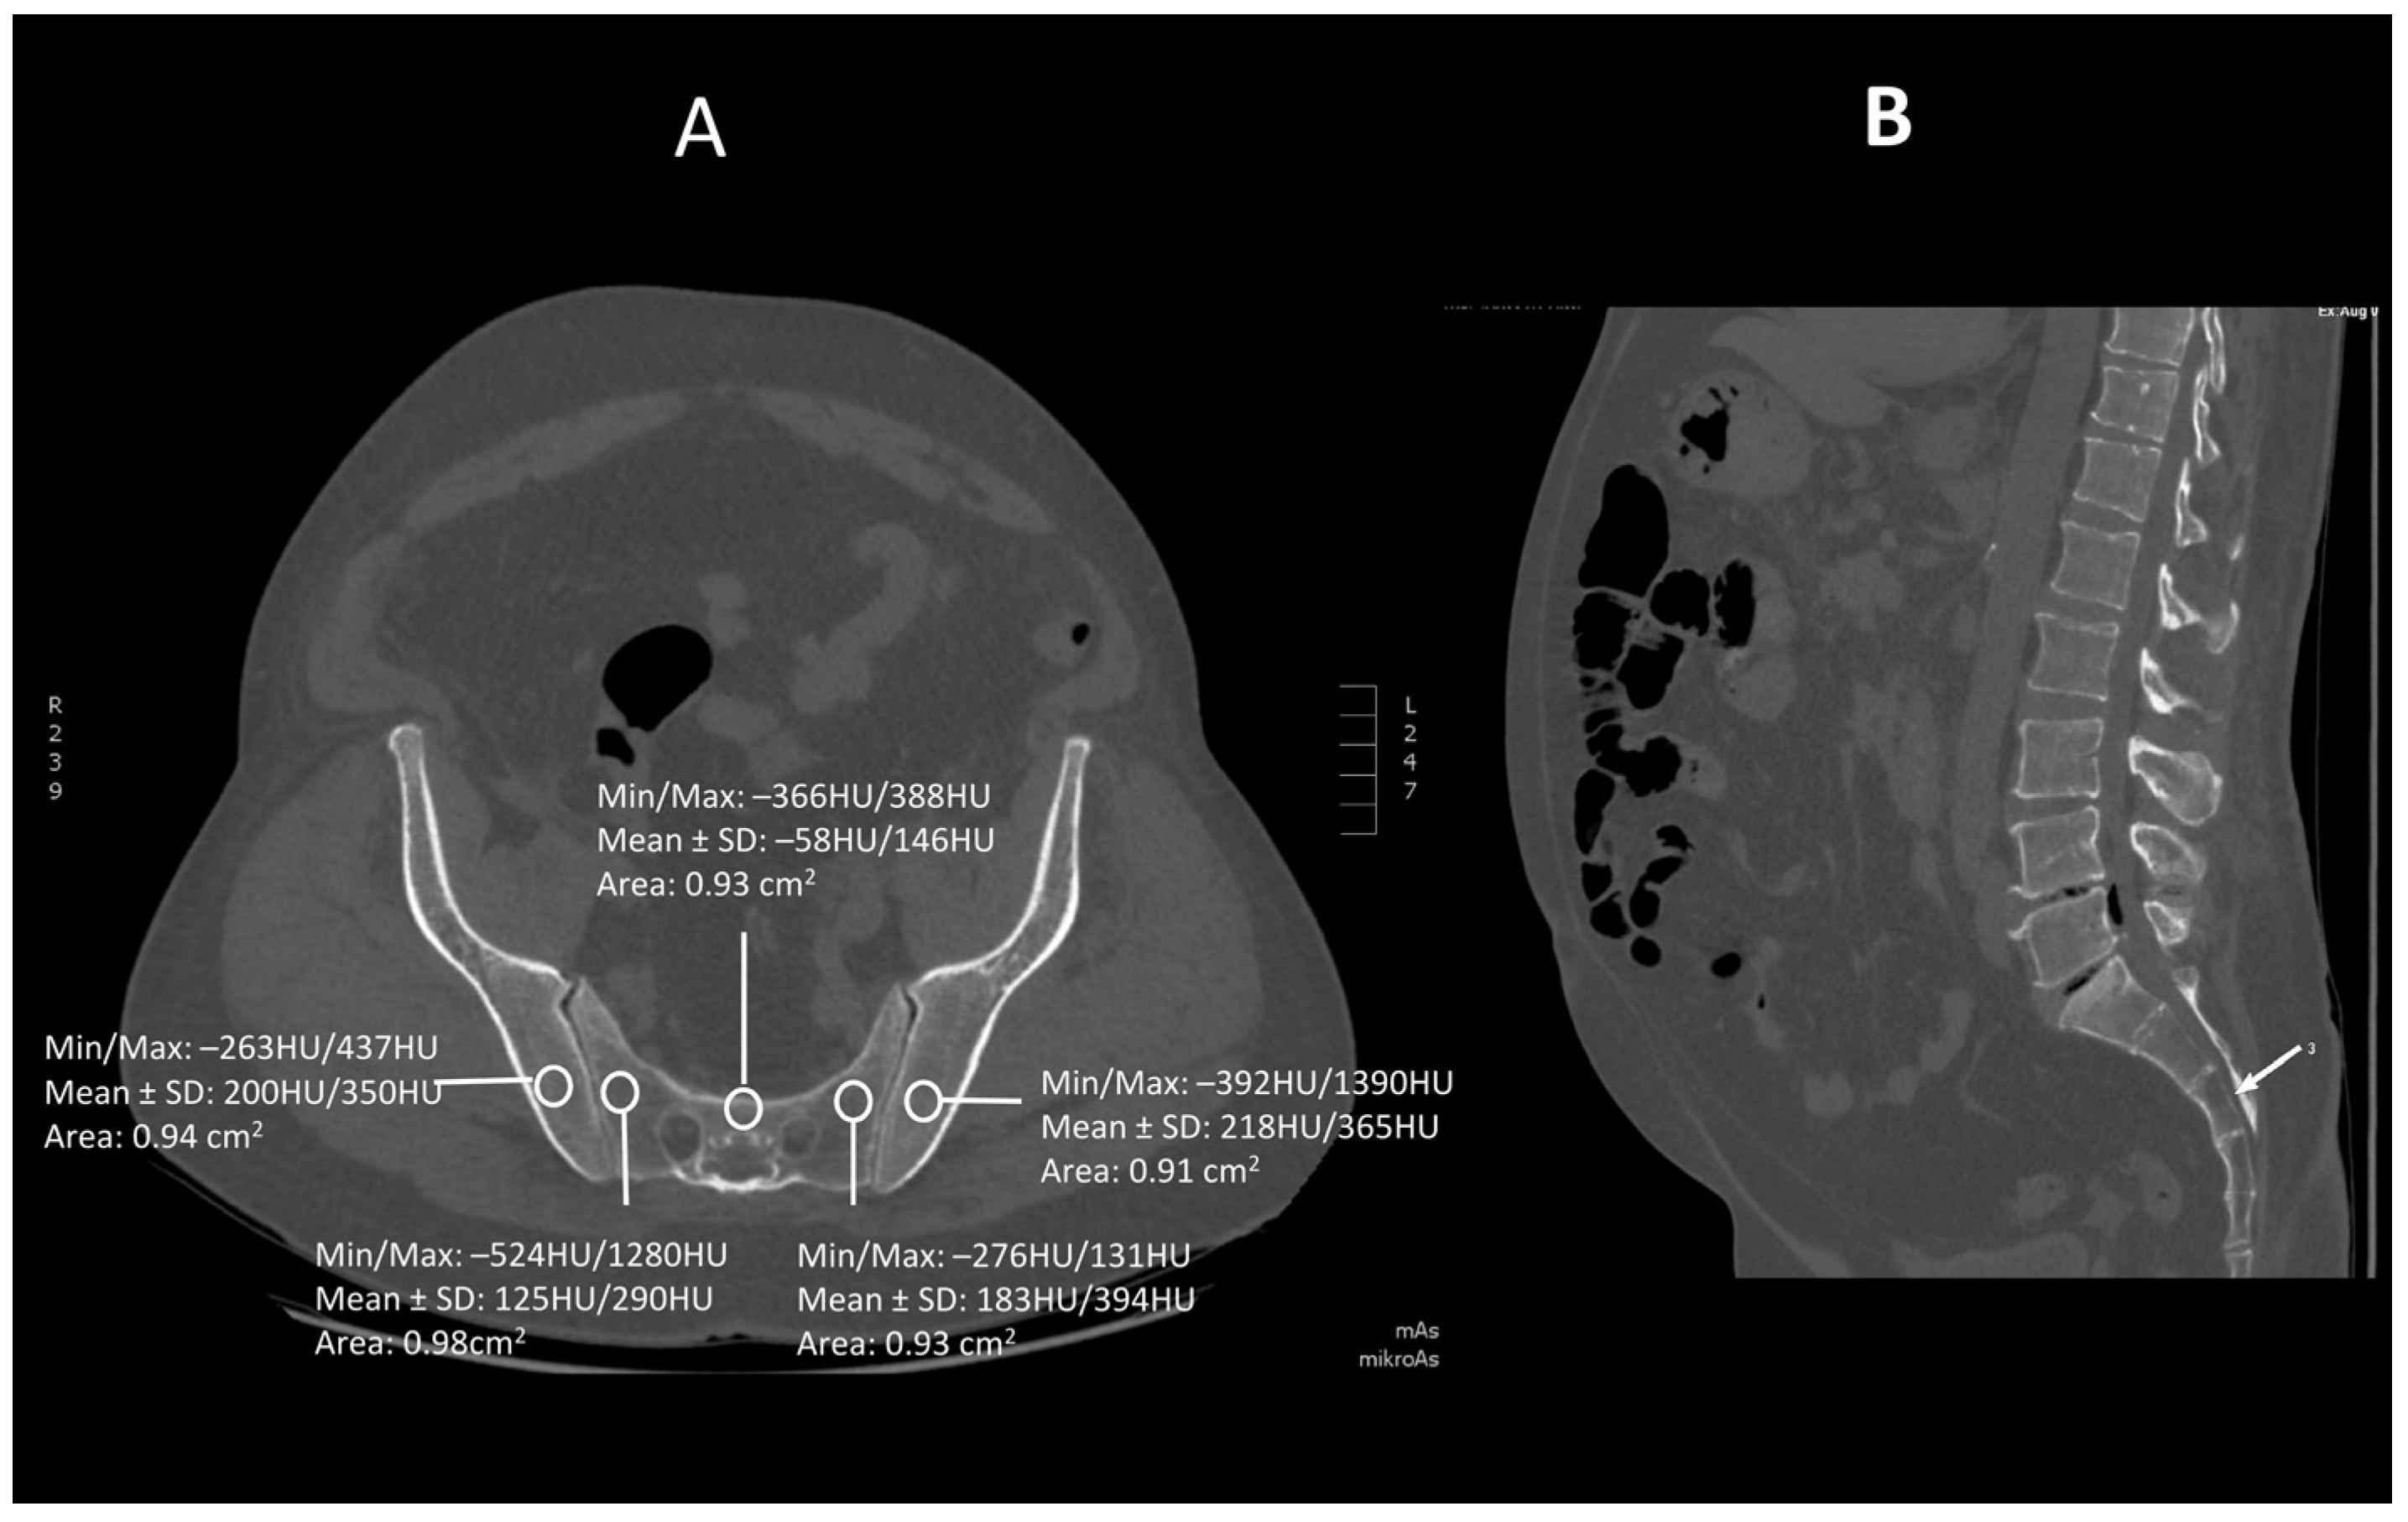

Figure 2.

A transverse (A) and saggital (B) projection of CT scan in level S2. A circular region of interest (ROI) ranging from 0.8 to 1.2 cm2 has been placed at the ala of the ilium, the wing of the sacrum and the tbody of sacral vertebra 2.

Images were viewed using the bone algorithm default windows. The investigator first determined axial images in levels of mid-lengths of bodies of sacral vertebrae 1, 2 and 3 that afterward were confirmed by coronal and sagittal reconstructions (Figure 1, Figure 2 and Figure 3). The volumetric bone density expressed in HU values was measured in sacral levels of S1, S2 and S3. Apart from the bodies of sacral vertebrae S1–S3, the measurements involved the ala of the ilium in the vicinity of the sacroiliac joint and the wing of the sacrum. All the measurements were performed on the pathway of presumptive iliosacral screws to stabilize the sacroiliac joint.

In order to standardize measurements while accounting for normal anatomic variations and optimum iliosacral screw trajectories—so as to avoid injuries of neurovascular structures—standardized circular voxel regions of interest (ROIs) were drawn (Figure 1, Figure 2 and Figure 3) [12]. As presented in the former studies, these ROIs were drawn in levels of mid-lengths of the bodies of sacral vertebrae 1, 2 and 3, the right and left wings of sacrum and the ala of the ilium in sacral levels of S1–S3 [13]. The aforementioned standardized ROIs were drawn with areas ranging from 0.8 to 1.2 cm2. This range of area was estimated as it best represented the osseous surface area, which is required to safely place 7.0–mm iliosacral or transsacral screws [4].